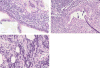

Results: We identified 48 AIP cases: 30 from literature review, 14 from INSPPIRE, and 4 from CUSL. The median age at diagnosis was 13 years (range 2-17 years). Abdominal pain (43/47, 91%) and/or obstructive jaundice (20/47, 42%) were the most common symptoms at diagnosis. Elevated serum IgG4 levels were only observed in 9/40 (22%) children. Cross-sectional imaging studies were abnormal in all children including hypointense global or focal gland enlargement (39/47, 83%), main pancreatic duct irregularity (30/47, 64%), and common bile duct stricture (26/47, 55%). A combination of lymphoplasmacytic inflammation, pancreatic fibrosis, and ductal granulocyte infiltration were the main histological findings (18/25, 72%). Children with AIP had a prompt clinical response to steroids. Complications of AIP included failure of exocrine (4/25, 16%) and endocrine (3/27, 11%) pancreas function.